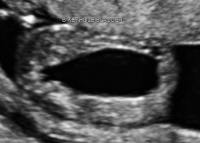

Lower Urinary Tract Obstruction (LUTO)

Lower urinary tract obstruction (LUTO) refers to a blockage in the urinary tract that restricts or prevents the release of urine from the bladder. Accumulation of urine within the kidneys and bladder throughout pregnancy results in permanent damage to these organs. If urine cannot exit the body, the amount of surrounding amniotic fluid decreases. Amniotic fluid is essential for normal lung development. LUTO occurs in about one in 5,000 births.

Luto keyhole bladder